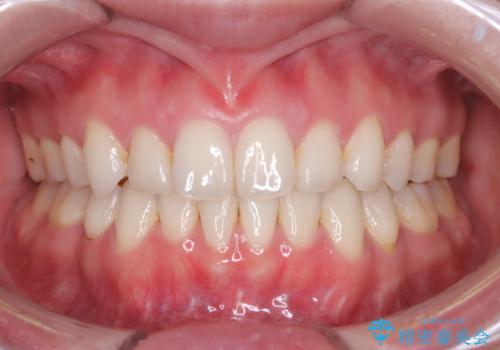

今回の治療で最も重要だったのは、患者様のご要望通り既存のセラミックブリッジを外さずに矯正を進める点でした。計画通り右上の小臼歯を抜歯し、透明なインビザラインを使用して抜歯スペースを閉じながら、八重歯を正しい位置へ移動させました。ブリッジの形態と調和するに、他の歯の移動を工夫をすることで、複雑な条件をクリア。治療の結果、長年気にされていた八重歯が解消され、見た目が大きく改善しました。50代からでも、ご自身の要望を叶えながら、美しく機能的な歯並びを獲得していただけました。